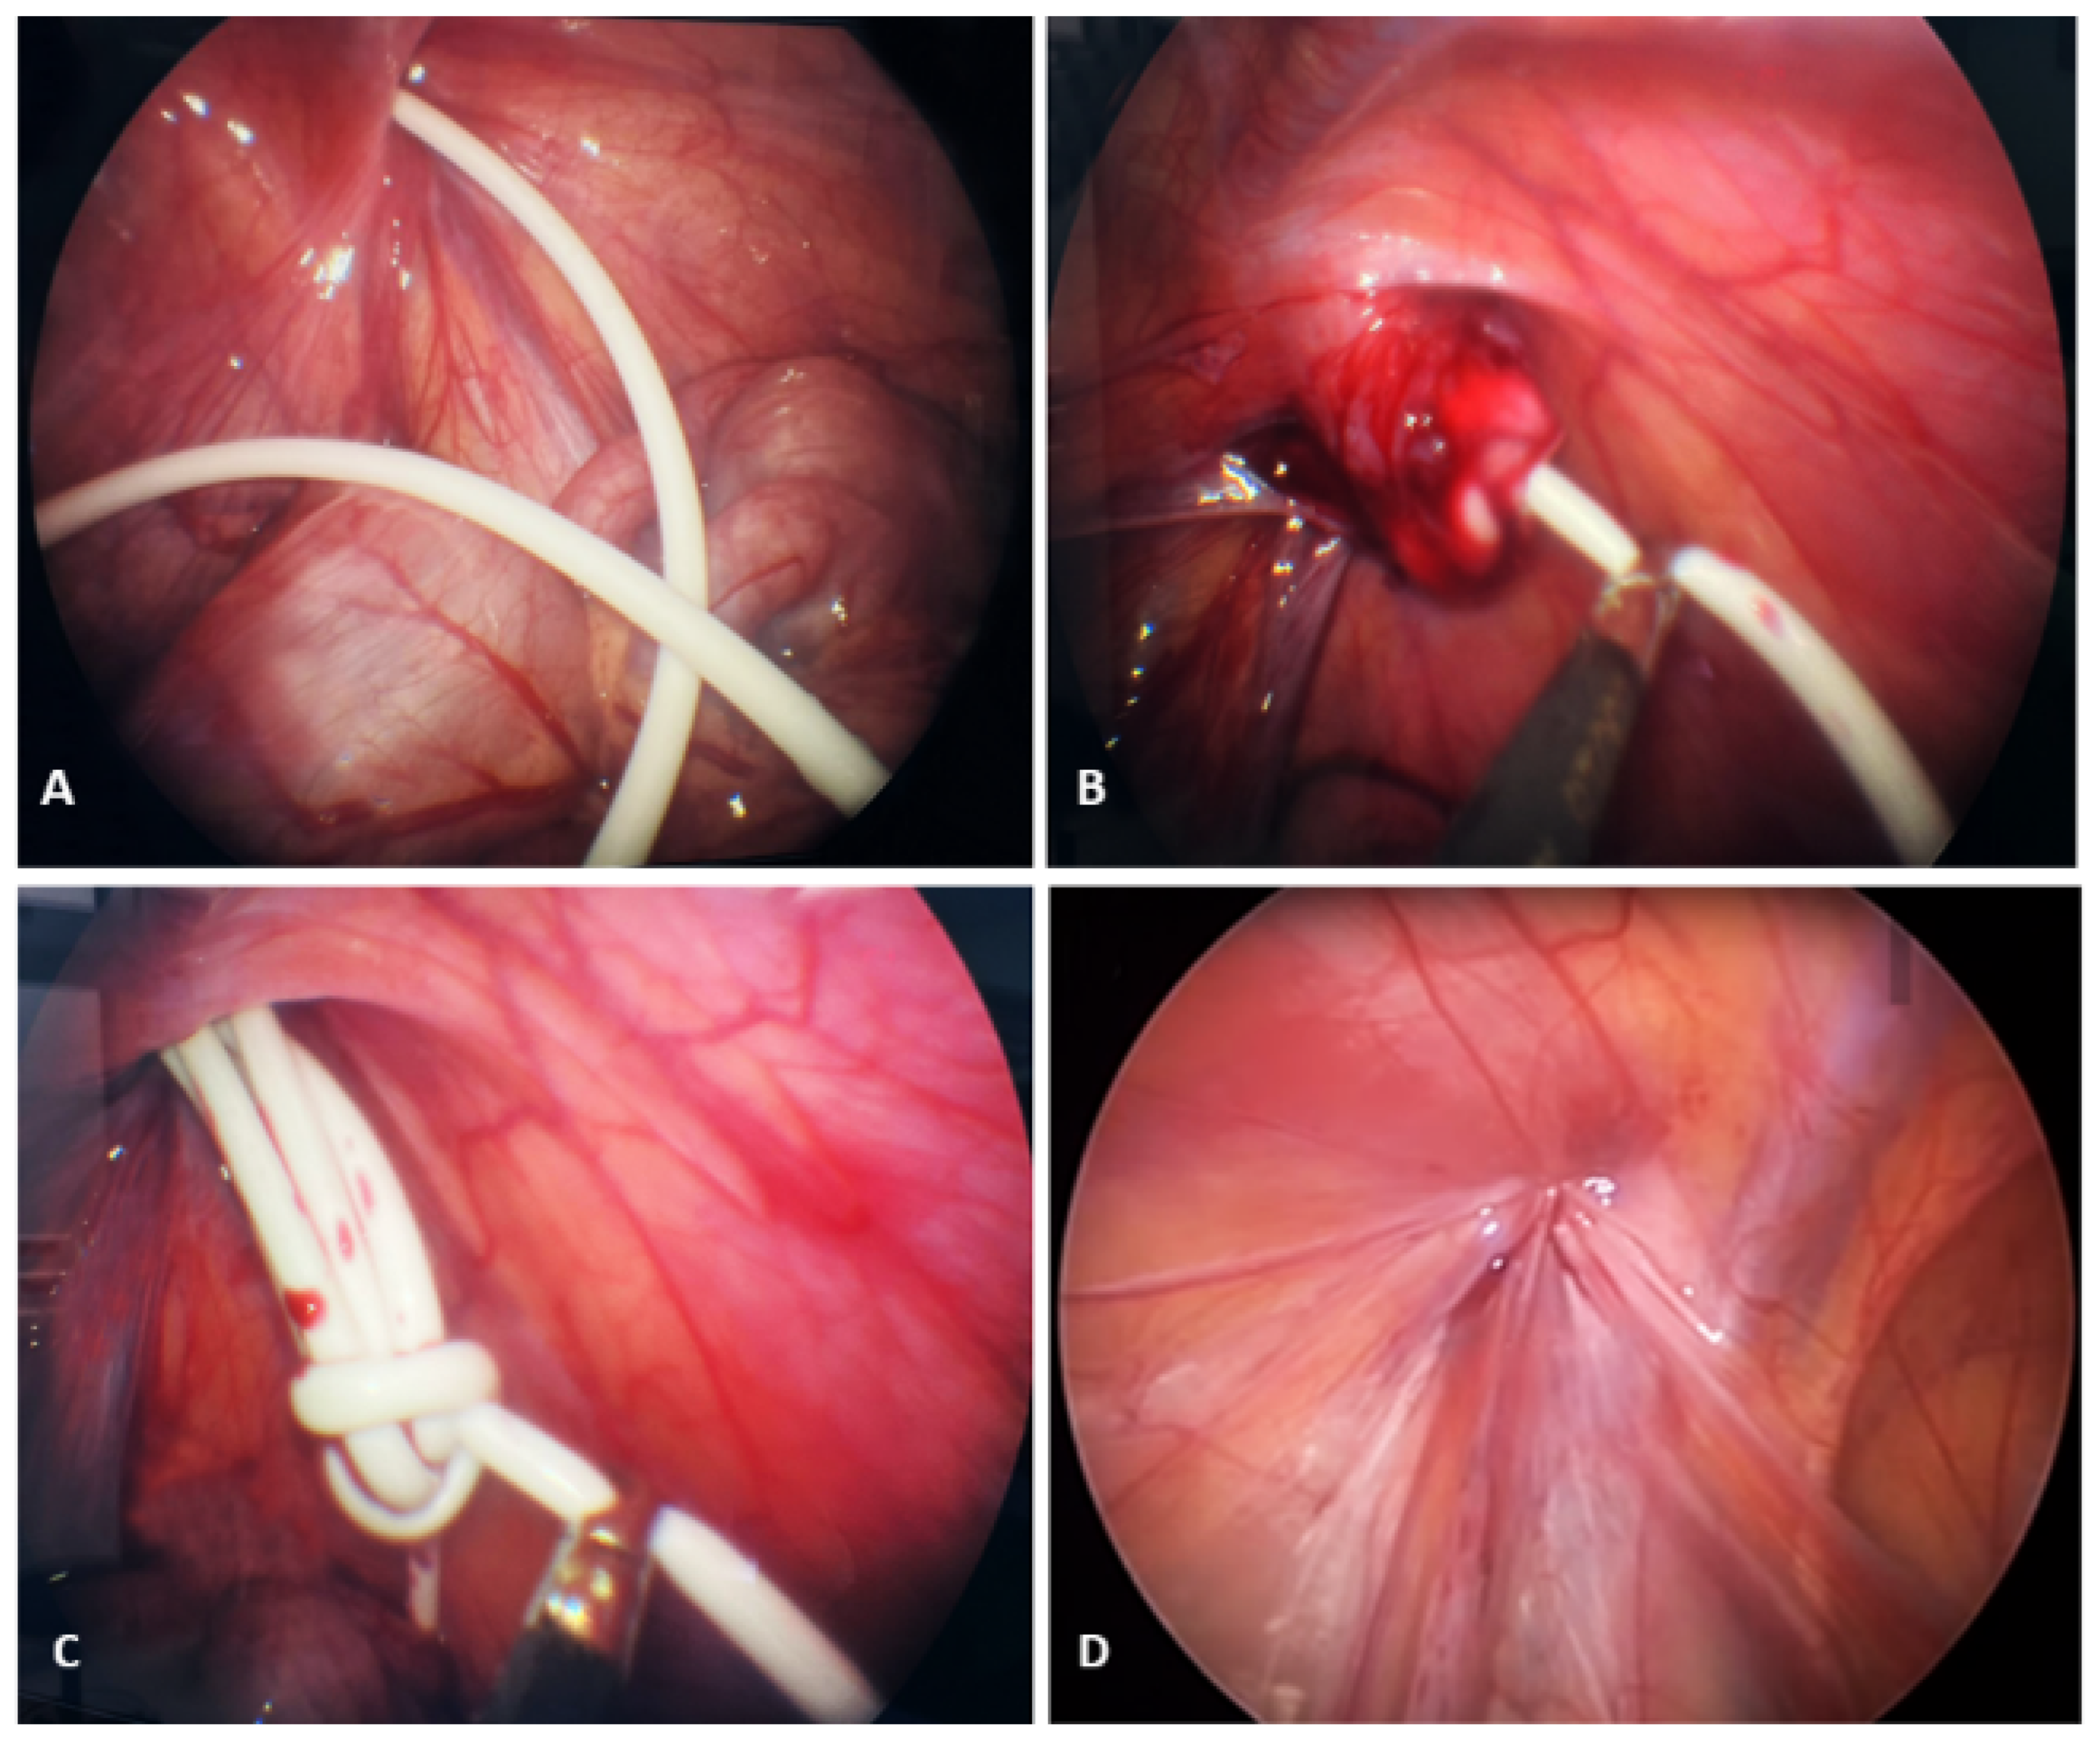

| Muhajir et al. [19] | Case 1. Shortening the VPS distal tip catheter and repositioning of VPS into the peritoneal cavity. Case 2: Distal exteriorization of the VPS catheter tip and repositioning of VPS into the peritoneal cavity. Case 3: Shortening the distal tip VPS catheter and repositioning of the VPS into the peritoneal cavity. High ligation of the PV. | None | None | 3, 3, 3 | 0 | NA |

| Ezzat et al. [27] | Repositioning of VPS into the peritoneal cavity (1 laparotomy, and 2 laparoscopy). | None | None | NA | 0 | NA |